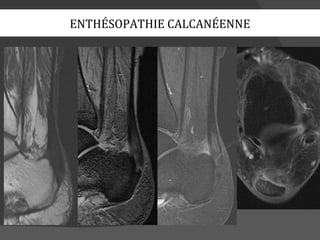

ENTHÉSOPATHIE CALCANÉENNE